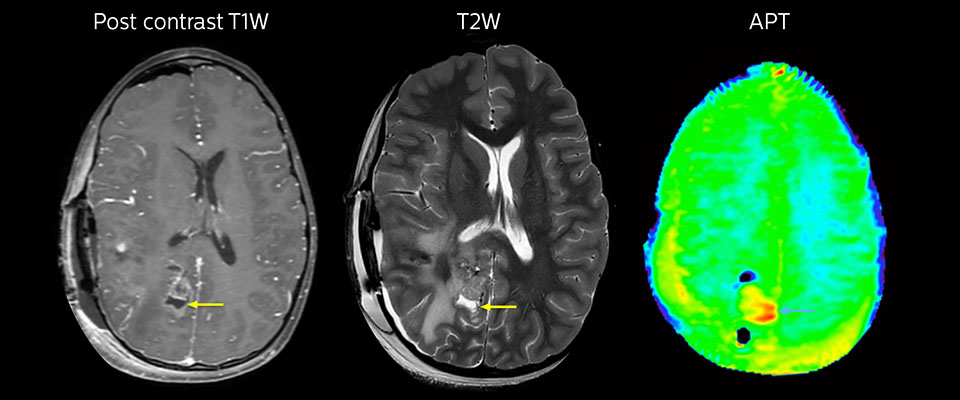

APT may illuminate post-resection images with crucial information

MRI may be performed after tumor resection, to look for residual tumor or tumor regrowth. Also here, the different contrast mechanism of APT may help in diagnosis. Dr. Miller remembers a particular case.

“After a very good resection, we saw small changes on the postcontrast T1-weighted and the T2-weighted images that looked like a post-surgical little bit of fluid. Interestingly, however, we saw a focal area of APT signal, right in the center of that abnormality. As we usually do when a bit unsure, we followed it up and, unfortunately, found tumor regrowth in that region,” Dr. Miller says. “Cases like this motivate me, and others who care about this population, to investigate how this APT method could be used on large scale in this population and help us in providing high value diagnostic information.”

MRI with APT post resection

Immediately post resection MRI was again performed. T2-weighted and postcontrast T1-weighted images are quite inconclusive for distinguishing residual tumor tissue from postoperative tissue changes. On the APT image some high signal is still seen, which would suggest residual tumor tissue.

Follow-up over time results

Follow-up over time

In later follow-up scans the post-contrast T1-weighted images suggest recurrent tumor growth. So, it would be interesting to study the predictive value of APT in a large patient group.